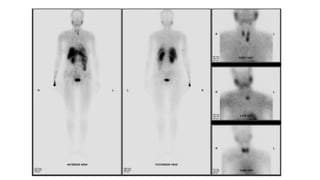

When the radiopharmaceutical is used for parathyroid imaging,

immediate and delayed imaging of the neck and mediastinum is

performed; parathyroid adenomas are best demonstrated on

delayed imaging (1-2 hours). A thyroid scan using Tc-99m

pertechnetate follows. Parathyroid adenomas do not demonstrate

uptake on thyroid scans, whereas normal thyroid tissue does.

• Immediately caudal to the left thyroid lobe, there is punctate uptake in the early phase (15 min registration) that remains

active during the late phase (2 hours). The localization of this uptake matches the lesion identified on MRI confirming

parathyroid adenoma.